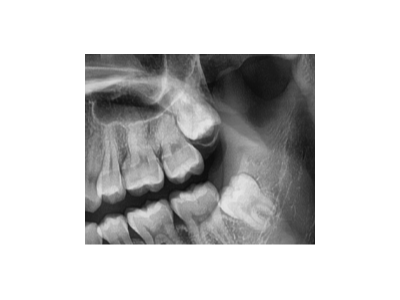

牙齒松動(dòng)只能拔?松牙固定術(shù)來(lái)“救場(chǎng)”!

牙齒松動(dòng)最佳補(bǔ)救方法

牙齒松動(dòng),不一定要拔牙。如果及時(shí)檢查治療,符合保留條件的松動(dòng)牙通常是可以固定修復(fù)的。松動(dòng)牙固定后穩(wěn)固有力,可以盡情享受美食!”